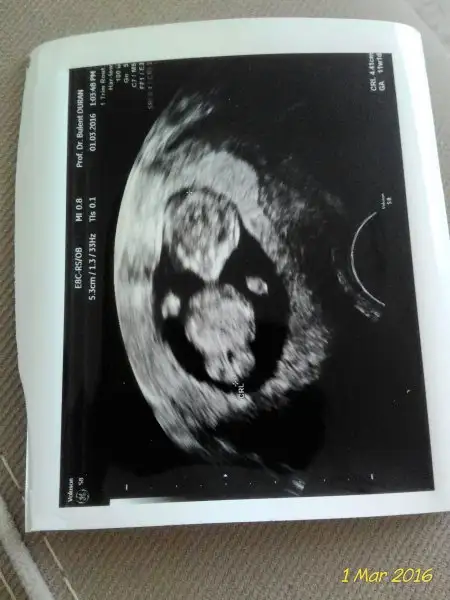

kızlr benimkini de yorumlar mısnız? sat a göre 8 usg ye göre 8+5 karından ultrason görüntüsü bu.

birde buraya yükliyeyim :) sata göre 10+4 usg ye göre 11+1 alttan muayene